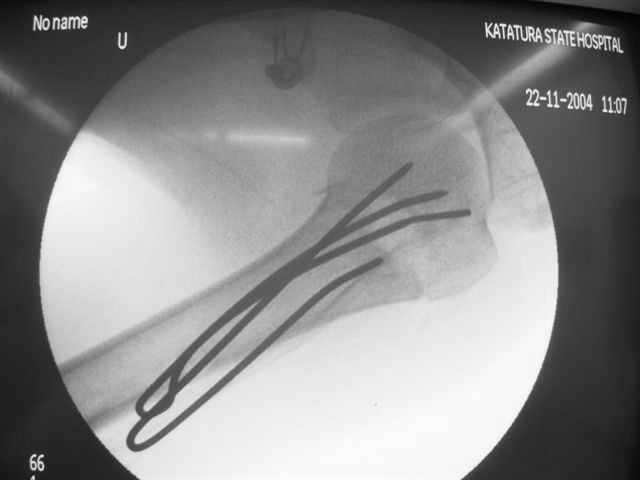

Здравствуй Женя. Во первых спицы, вводимые в головку плеча ретроградно, никогда не имели V-образную форму, если говорить о методике моей операции ЦИТО. Чтобы легче было запомнить Y-образную форму, вспомни крепление новогодних елочных шаров - очень демонстративно. Кроме того если ты внимательно посмотришь, то увидишь, что вся конструкция имеет некоторую кривизну по плокскости, величину, которой ты можешь задать сам. Сначала мы проводим проксимальный пучок, а в момент пересечения линии перелома мы

ротируем спицу таким образом, чтобы дистальный изгиб прямо противодействовал смещающим силам - поврот за ушко под контролем ЭОПа. Дистальный пучок стараемся провести так, чтобы его бранши расклинились и прошли по обе стороны предыдущего пучка, что создает дополнительное напряжение на

протяжении контакта. Для оценки правильности проведения спиц очень важно, чтобы ЭОП стоял строго перпендикулярно плоскости сустава, в противном случае - в рентгене есть эффект отбрасывания тени - прохождение косого луча дает удлиненное изображение спиыц и создается впечатление, что спица стоит уже в субхондральном слое. На первых операциях у нас было довольно частое несовпадение длины контрольной спицы и мы провизорно добавляли от 0,5 до 1,0 см уже на фиксирующем пучке. Входные отверстия лучше располагать по наружной и передней поверхности плеча на расстоянии не менее 2-х диаметров головки.

Такой выбор входных отверстий обусловлен прямой возможностью попадания в малый и большой бугорки за счет изгиба спиц по длине и отражения из от внутреннего кортикала проксимальнее точки введения. Поскольку анатомически бугорки не составляют артикулирующую поверхность, то некоторое выстояние спиц только усилит стабильность. Входное отверстие мы используем 6 мм в диаметре, для эффективного раскрытия петли-пружины. Спицы перед проведением

проверяем на достаточную эластичность и упругоустойчивость, мягкие спицы отбраковываем. В данном примере создалось впечатление, что одна бранша V-спицы скользнула по картикалу снаружи? Все это безболезненно можно переделать, расширив теже отверстия, изогнув спицы, повернув их в разные стороны и добавив еще пучки Y-ОБРАЗНЫХ, а не V-образных (эти пучки выталкивает, особенно если они прямые - пружина работает в обе стороны).